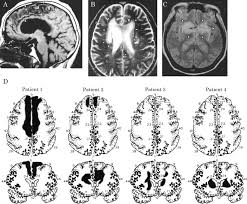

Bilateral anterior cerebral artery (aca) territory infarction is rare and its associated symptoms are still not well understood. Cerebral infarcts in the territory of the anterior cerebral artery (aca) are infrequent and yet few studies have specifically assessed the clinical characteristics of stroke patients with aca infarction .so far, single case reports and small series of aca stroke have been reported and, in most cases, patients with aca infarction are included in group of hemispheric cerebral infarction as a. Hemiparesis, sensory deficits, and ataxia can occur with either a right or left hemisphere lesion and typically affect the contralateral side. The anterior cerebral artery supplies blood to most of the anterior section of the interhemispheric cortical surface of the frontal and parietal lobes (physiopedia 2016). The mean age of the cohort was 71 years.

The mean age of the cohort was 71 years. A solid understanding of the pathophysiology of a posterior cerebral artery (pca) stroke as well as the syndrome relating to it, requires adequate knowledge of the structures and vascular anatomy of the brain. The test is positive if ≥ 1 is present. In 1943, adams1 was the first to completely describe the syndrome associated with the aica occlusion. The common clinical features were various primitive reflexes and parkinsonian symptoms including akinesia, rigidity and hypophonia. •posterior cerebral artery (occipital lobe, thalamus, medial temporal lobe) •brainstem (midbrain, pons, medulla) •cerebellum •recognize four common lacunar stroke syndromes •pure motor stroke •pure sensory stroke Ischemic stroke is the most common of the three types of stroke. We evaluated the clinical symptoms of four patients with bilateral aca infarction. It`s important to recognise the stroke symptoms and to immediately seek medical assistance. Fast (face, arm, speech, time) has a sensitivity of 82% and a specifity of 83%. It's also referred to as brain ischemia and cerebral ischemia. Clinical, mri, and angiographic findings of 100 consecutive patients with aca infarction were studied. Findings in aca stroke may include the following:

Fast (face, arm, speech, time) has a sensitivity of 82% and a specifity of 83%. Findings in aca stroke may include the following: In his patient, neurotologic symptoms such as. We evaluated the clinical symptoms of four patients with bilateral aca infarction. If the anterior inferior cerebellar artery becomes blocked, a stroke can occur.

Stroke Neupsy Key from neupsykey.com Fast (face, arm, speech, time) has a sensitivity of 82% and a specifity of 83%. Stroke mechanisms and clinical features of anterior cerebral artery (aca) territory infarction have rarely been investigated using mri. Clinical, mri, and angiographic findings of 100 consecutive patients with aca infarction were studied. We studied the topographical distribution of the lesions and the resulting clinical effects for a better understanding of their relationship and the functional outcome. The internet stroke center n.d.b) anterior cerebral artery stroke. It is characterized by weakness and sensory loss in the lower leg and foot opposite to the lesion and behavioral changes. The mean age of the cohort was 71 years. The anterior inferior cerebellar artery (aica) is responsible for carrying blood to the cerebellum.